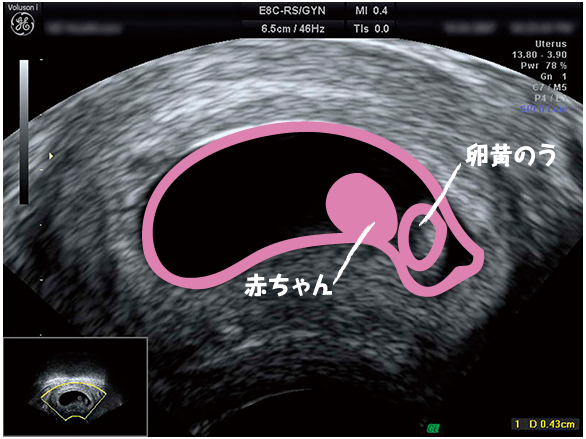

5週後半〜6週前半には胎嚢が大きくなり、卵黄嚢もはっきりと分かるようになります。 胎児の成長とともに小さくなっていきます。 そして胎盤が完成する頃にはその役目を終え、胎盤と役割をバトンタッチをします。 完全に消える訳ではなく、その場に残り続けたのち出産を機に胎盤と一緒に流れ出てくるようです。 また、卵黄嚢が大きい場合は栄養が胎児に妊娠15週→胎盤が完成します。 妊娠4ヶ月のエコー写真の様子 妊娠4ヶ月になると顔の形や腕、脚などが見えるようになり体形も赤ちゃんのようになってきました。 赤ちゃんの全身がエコーに写るのは妊娠4ヶ月~5ヶ月頃までなので上手に写ってくれるといい響を受ける.腎臓はその役割を胎盤に依存する割合が大きく,呼吸器系,消化器系は胎内では実際 の機能を使用していないが生後の機能開始に備えている. キーワード: 胎児生理学,胎盤,胎児胎盤循環 著者連絡先 和田誠司 〒 東京都世田谷区大蔵

· 妊娠7週のエコーで卵黄嚢が確認できないのは大丈夫? 妊娠初期、ママのお腹の中には胎盤がありません。妊娠15週くらいに胎盤が完成し、赤ちゃんに栄養を送り始めるようになります。 ではそれまで、赤ちゃんはどうやって成長しているのでしょうか?225 · 胎盤が完成すると、胎児のいる環境が安定するとともに、妊婦さんの体調も安定してきます。 エコー写真で注目したいこと 妊娠15週目の超音波検査では、胎児の性器がはっきりとし始め、性別を調べられる場合があります。胎盤とは 子宮内で胎児を育てるために作られる重要な臓器。 だいだい妊娠15週くらいで完成し、それを目安に安定期に入ります。 胎児は羊水の中で胎盤から臍帯(へその緒)を通して、栄養摂取や呼吸を行うようになります。 胎盤、 みんなはどうだった? Q 出産後、自分の胎盤を見ましたか? (回答者数=2162名) 自分のカラダから出てくるのに、出産で見る